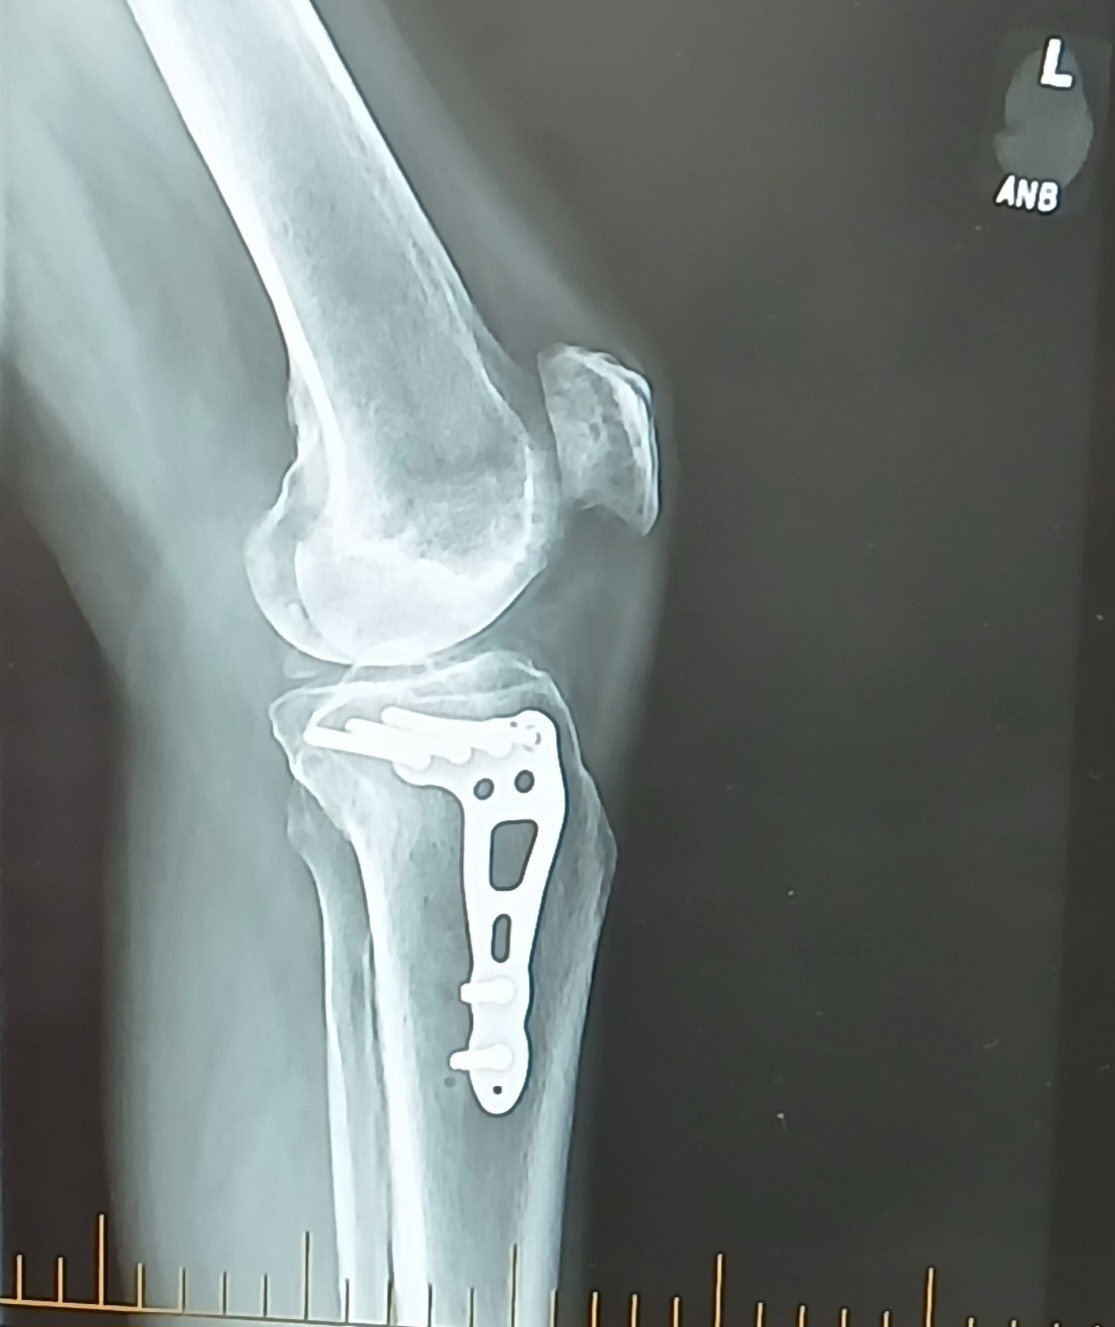

I am raising funds to help my husband I get back up from three significant devastations. The most traumatic and alarming is his left leg injury as a direct result of having been struck and pinned underneath a city owned truck. His tibia was badly fractured, with injuries that caused major financial setbacks in our lives. His surgery was on June 9th. He needed three months of healing and he is still recovering from there with physical therapy. His surgeon says that his foot will be swollen for a year. I personally haven't been able to escape the horrifying thought that if he were struck one split second sooner, it more than likely would have killed him. Right here is where I would like to install his narrative, directly from him: